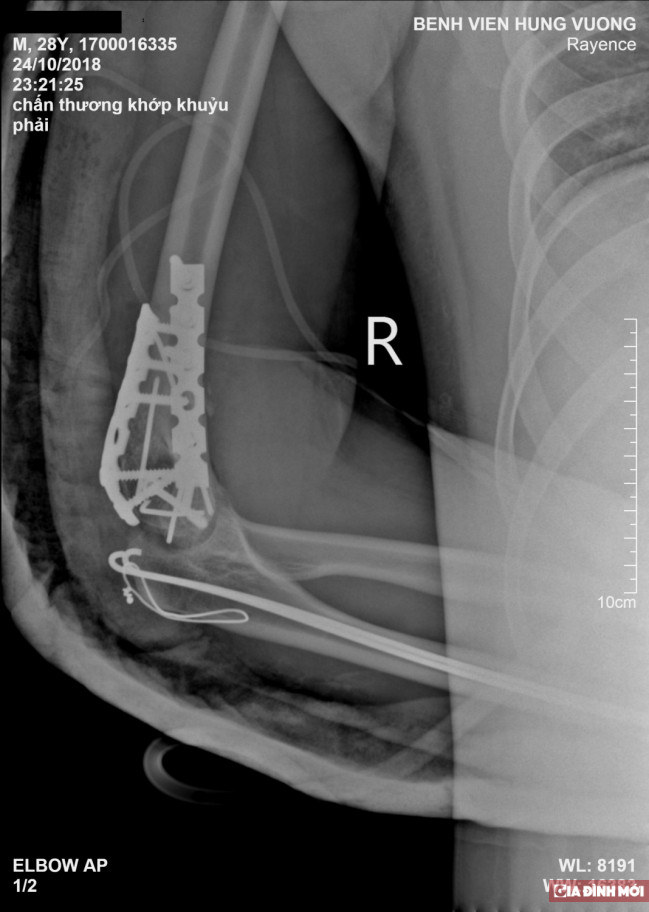

Tại đây, bác sĩ chẩn đoán bệnh nhân bị gãy liên lồi cầu cánh tay. Đây được đánh giá là một loại gãy khó, vị trí gãy là nơi có hố mỏm khuỷu và hố mỏm vẹt làm xương mỏng và yếu.

Bác sĩ Bệnh viện đa khoa Hùng Vương - nơi bệnh nhân cấp cứu nhận định, chấn thương của bệnh nhân khá nghiêm trọng, lồi cầu vỡ thành nhiều mảnh nhỏ nên khi phẫu thuật các bác sỹ cần phối hợp ăn ý và chính xác.

| Hình ảnh chụp X-quang cánh tay bị gãy của bệnh nhân |

Để tránh biến chứng về sau, cũng như phục hồi chức năng tay phải, bác sĩ đã đặt lại lồi cầu, kết hợp xương và nẹp vít 2 cột trụ, cố định mỏm khuỷu.